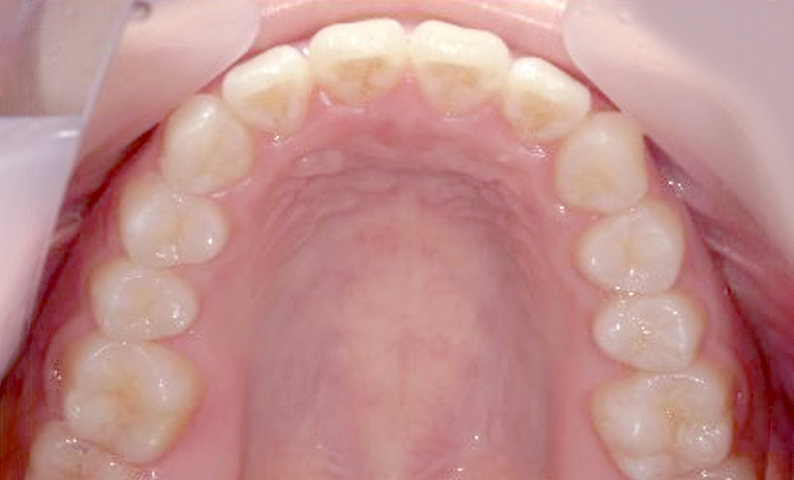

症例_004 上下顎の部分矯正

治療期間:8ヶ月金額:54万円+税女性前歯のガタガタ捻転歯

| Before | After |

|---|---|

|